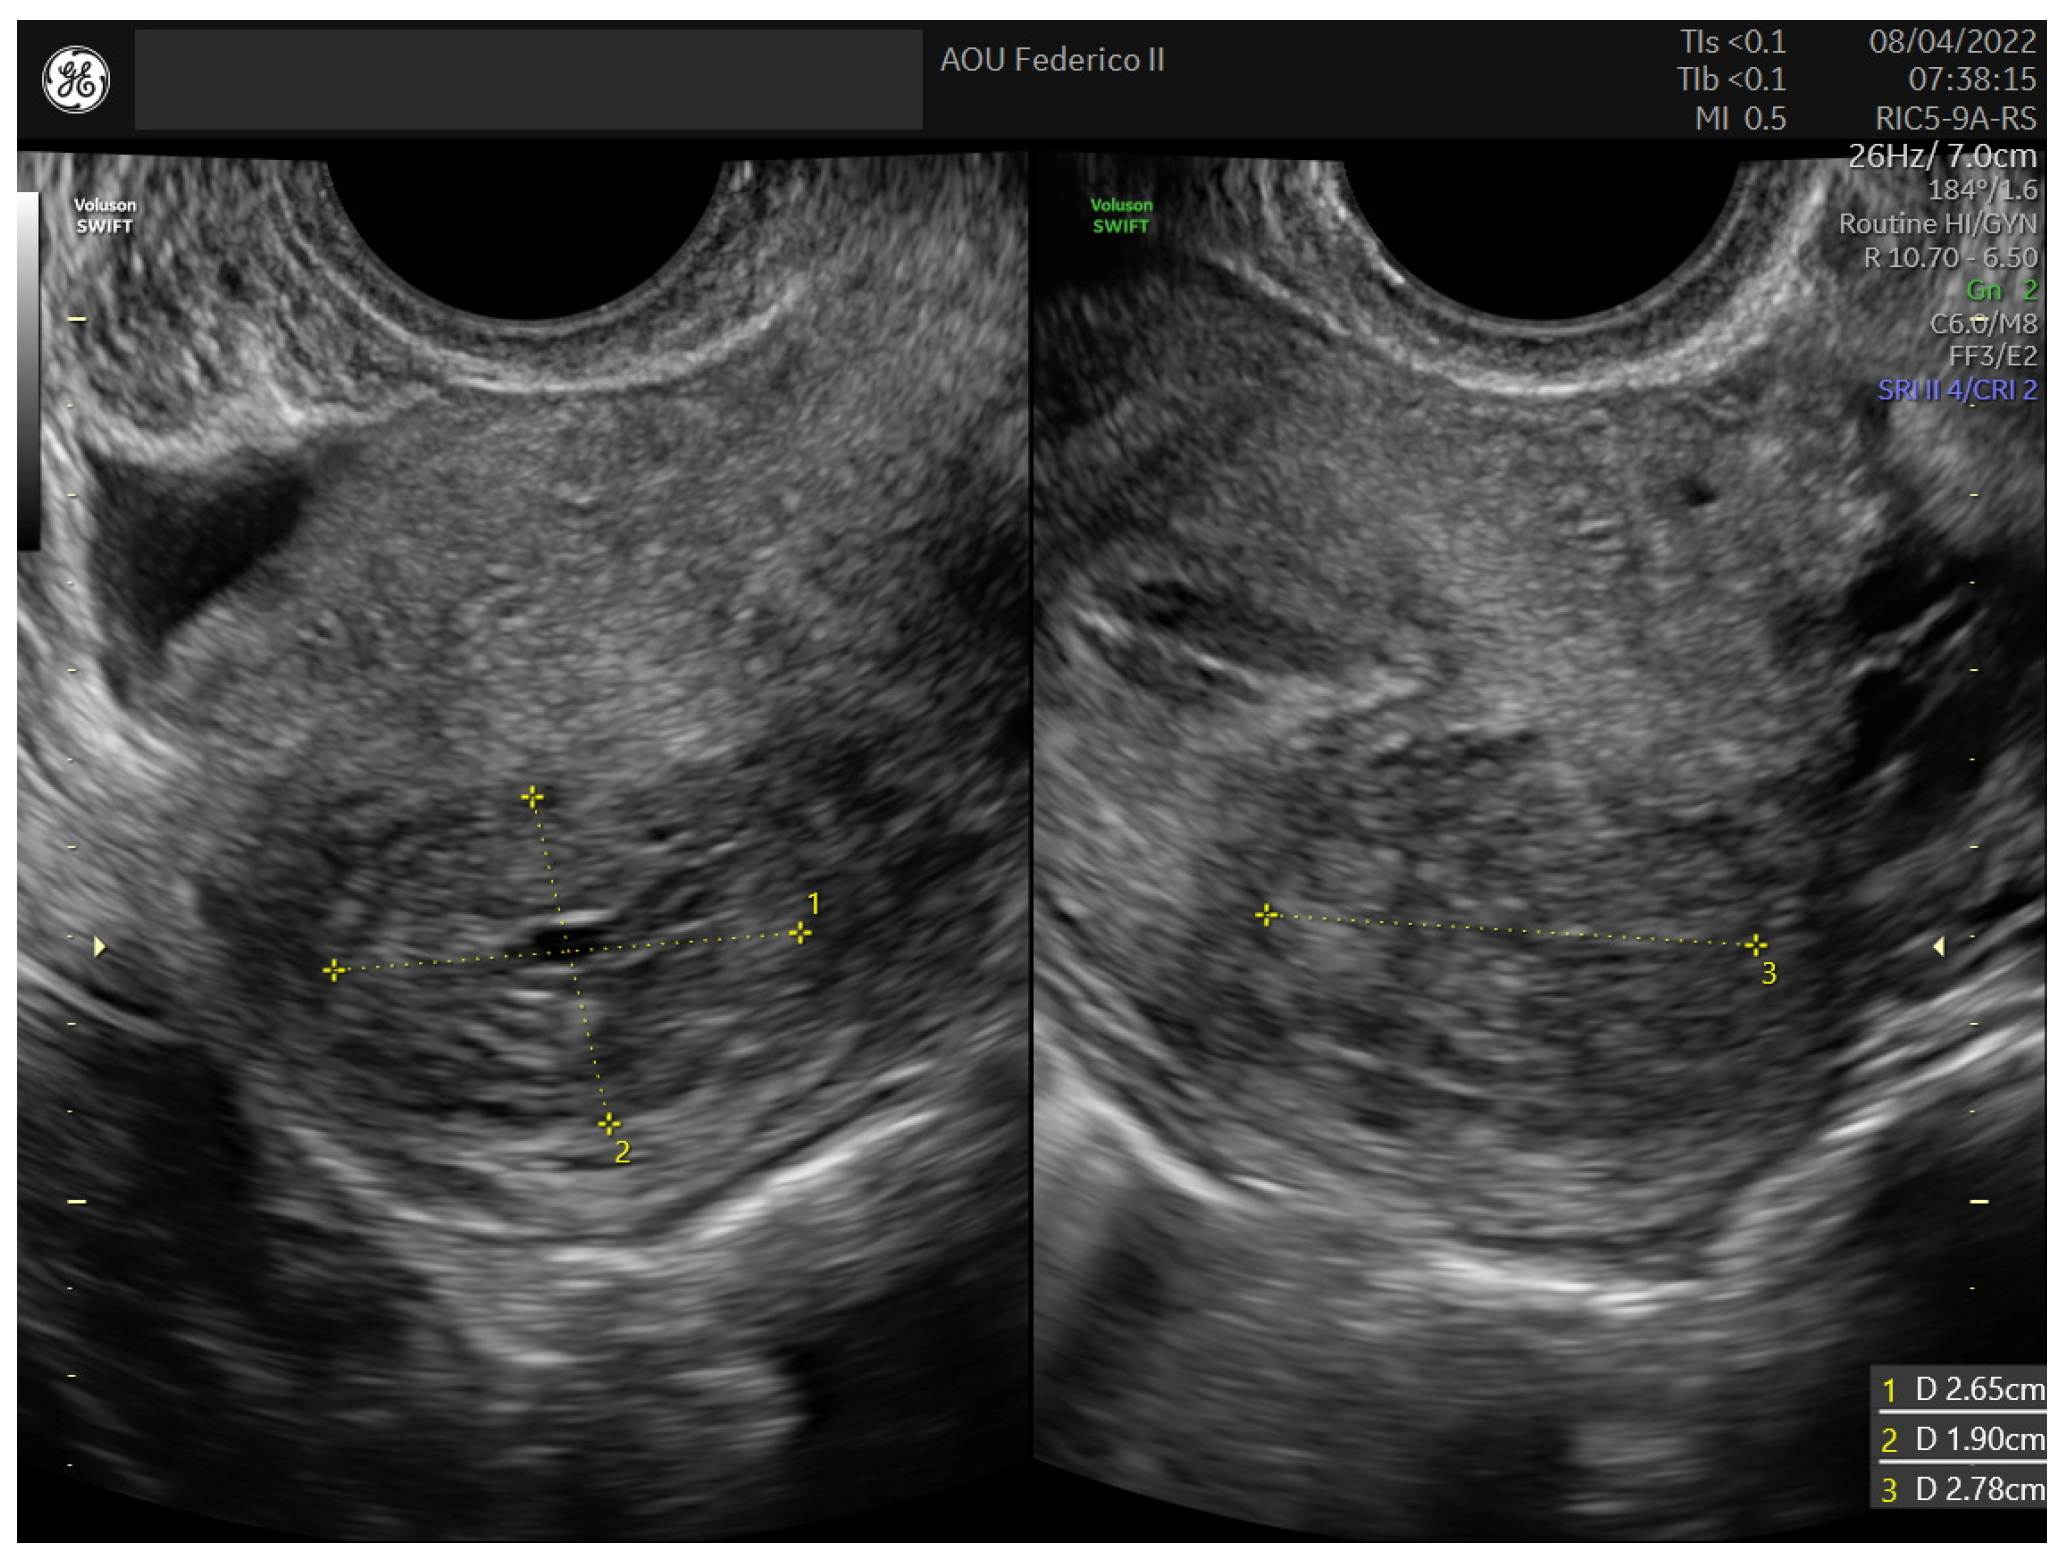

2.1. Case 1

2.2. Case 2